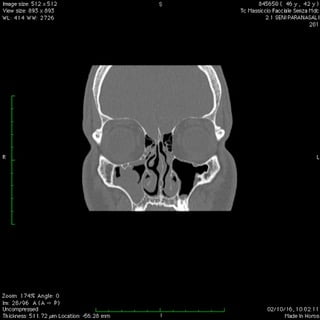

Anche nelle sinusiti la peculiare morfologia anatomica delle strutture coinvolte, cavità ossee, consente nella maggior parte dei casi latenze di esordio molto ritardate rispetto il primitivo insorgere patologico palesandosi così in avanzate fasi di compromissione .

Nelle forme croniche, cioè di malattia stabile nel tempo, i seni paranasali diventano “ siti di decantazione”, ovvero di ristagno e moltiplicazione,per germi di vario genere dando vita così ad un persistente primario serbatoio contaminante sia le vie aeree che quelle digestive.